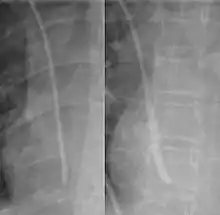

The line is then inserted using the Seldinger technique: a blunt guidewire is passed through the needle, then the needle is removed. A dilating device may be passed over the guidewire to expand the tract. Finally, the central line itself is then passed over the guidewire, which is then removed. All the lumens of the line are aspirated (to ensure that they are all positioned inside the vein) and flushed with either saline or heparin.[1] A chest X-ray may be performed afterwards to confirm that the line is positioned inside the superior vena cava and no pneumothorax was caused inadvertently. On anteroposterior X-rays, a catheter tip between 55 and 29 mm below the level of the carina is regarded as acceptable placement.[33] Electromagnetic tracking can be used to verify tip placement and provide guidance during insertion, obviating the need for the X-ray afterwards.

Chest x-ray with catheter in the right subclavian vein